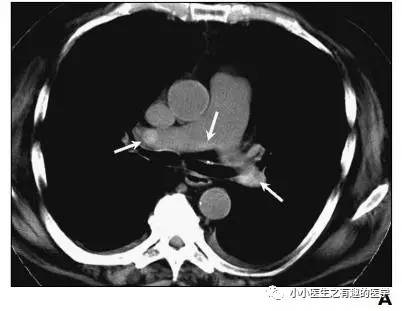

老外报道一例病人,门诊急诊CT平扫发现肺栓塞,但是病人危重,再次外出做增强CT很危险,别人直接高分辨CT诊断肺栓塞,直接治疗,病情缓解再出去检查。在中国,你懂的。(抱歉:有些文献下载要钱,穷,没有下载到)。

病例介绍三:

其实,我大中华也有医生用CT平扫发现可疑肺栓塞。

下面是上海交通大学的论文。

基本上看的到。